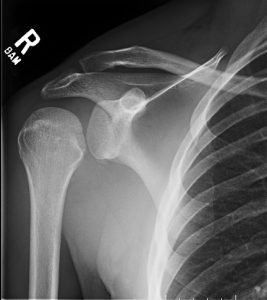

Posterior Shoulder Dislocation, AP XR. JETem 2017